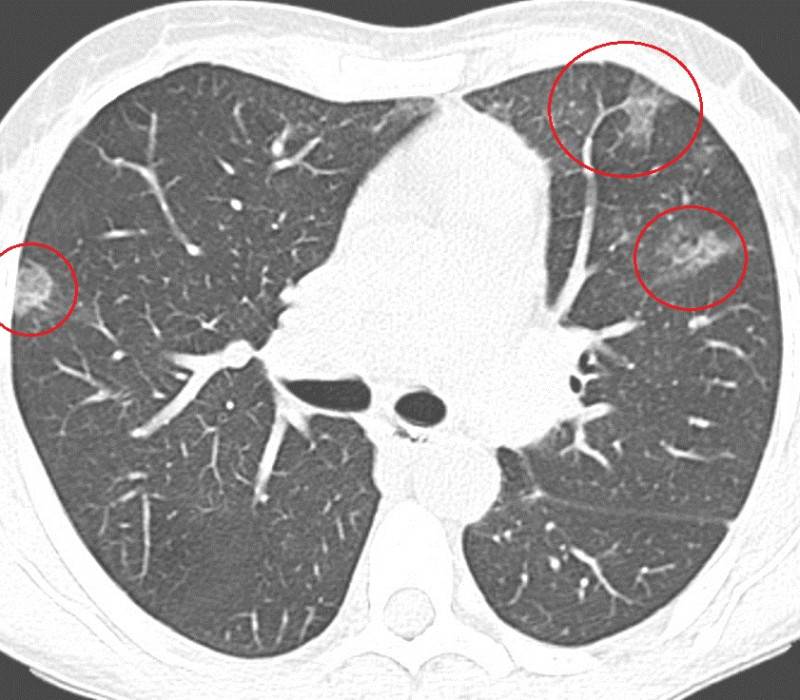

Достоверно выявить или исключить пневмонию можно только с помощью компьютерной томографии легких. На томограмме легких видны очаги поражения дыхательных путей («матовые стекла»). Лабораторные анализы помогут выявить специфических возбудителей воспаления легких по ответной реакции иммунной системы.

Разница на КТ-снимках

При сравнении снимков компьютерной томографии между коронавирусной и обычной пневмонией также отмечаются различия, причем довольно существенные. При COVID-19 обычно пневмония двусторонняя, и местом ее локализации является периферия легких, то есть непосредственно располагается под плеврой.

На начальных этапах заболевания она выглядит, по словам рентгенологов, как «матовое стекло». При дальнейшем прогрессировании пораженная область приобретает плотность и распространяется на большую площадь. После этого наступает стадия обратного развития – снижение плотности легочных инфильтратов и уменьшение их размеров.

В первую очередь назначается компьютерная томография легких, как наиболее информативное исследование. Такой вид диагностики дает более полную картину изменений в легких, что необходимо для назначения подходящей терапии. В то же время в стационаре пациент находится под пристальным наблюдением медицинского персонала, контролируются жизненные показатели, изменения в организме, такие как температура, частота дыхания и насыщение крови кислородом. Общий анализ крови недостаточен для контроля всех изменений в организме, проводятся дополнительные биохимические и другие исследования, в частности контроль коагулограммы. При этом необходим постоянный динамический контроль всех показателей для последующей индивидуальной медикаментозной корректировки. Слаженная работа медиков играет большую роль в борьбе с недугом.

Таким образом, для каждой вирусной пневмонии, в зависимости от типа возбудителя, характерен типический паттерн. Иногда уже по одному «рисунку» пневмонии на КТ-сканах возможно отличить, например, аденовирусную пневмонию от респираторно-синцитиального вируса. Для уточнения типа инфекционного возбудителя пациенту назначается лабораторное исследование (анализ отделяемого из носоглотки, ПЦР, тест на иммуноглобулины и др.).